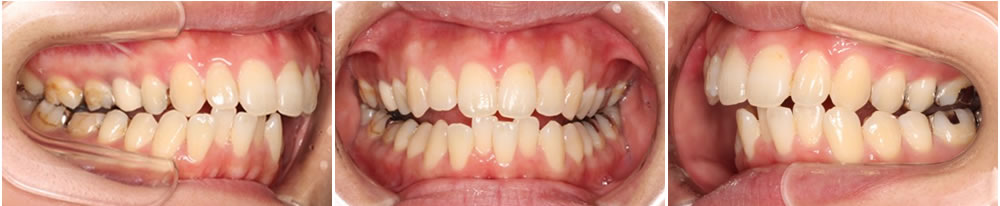

歯並びの比較

【矯正治療前 2017.1.11】

【矯正治療後 2021 .1.6】

アーチが大きく拡がり噛み合わせのバランスが整いました。